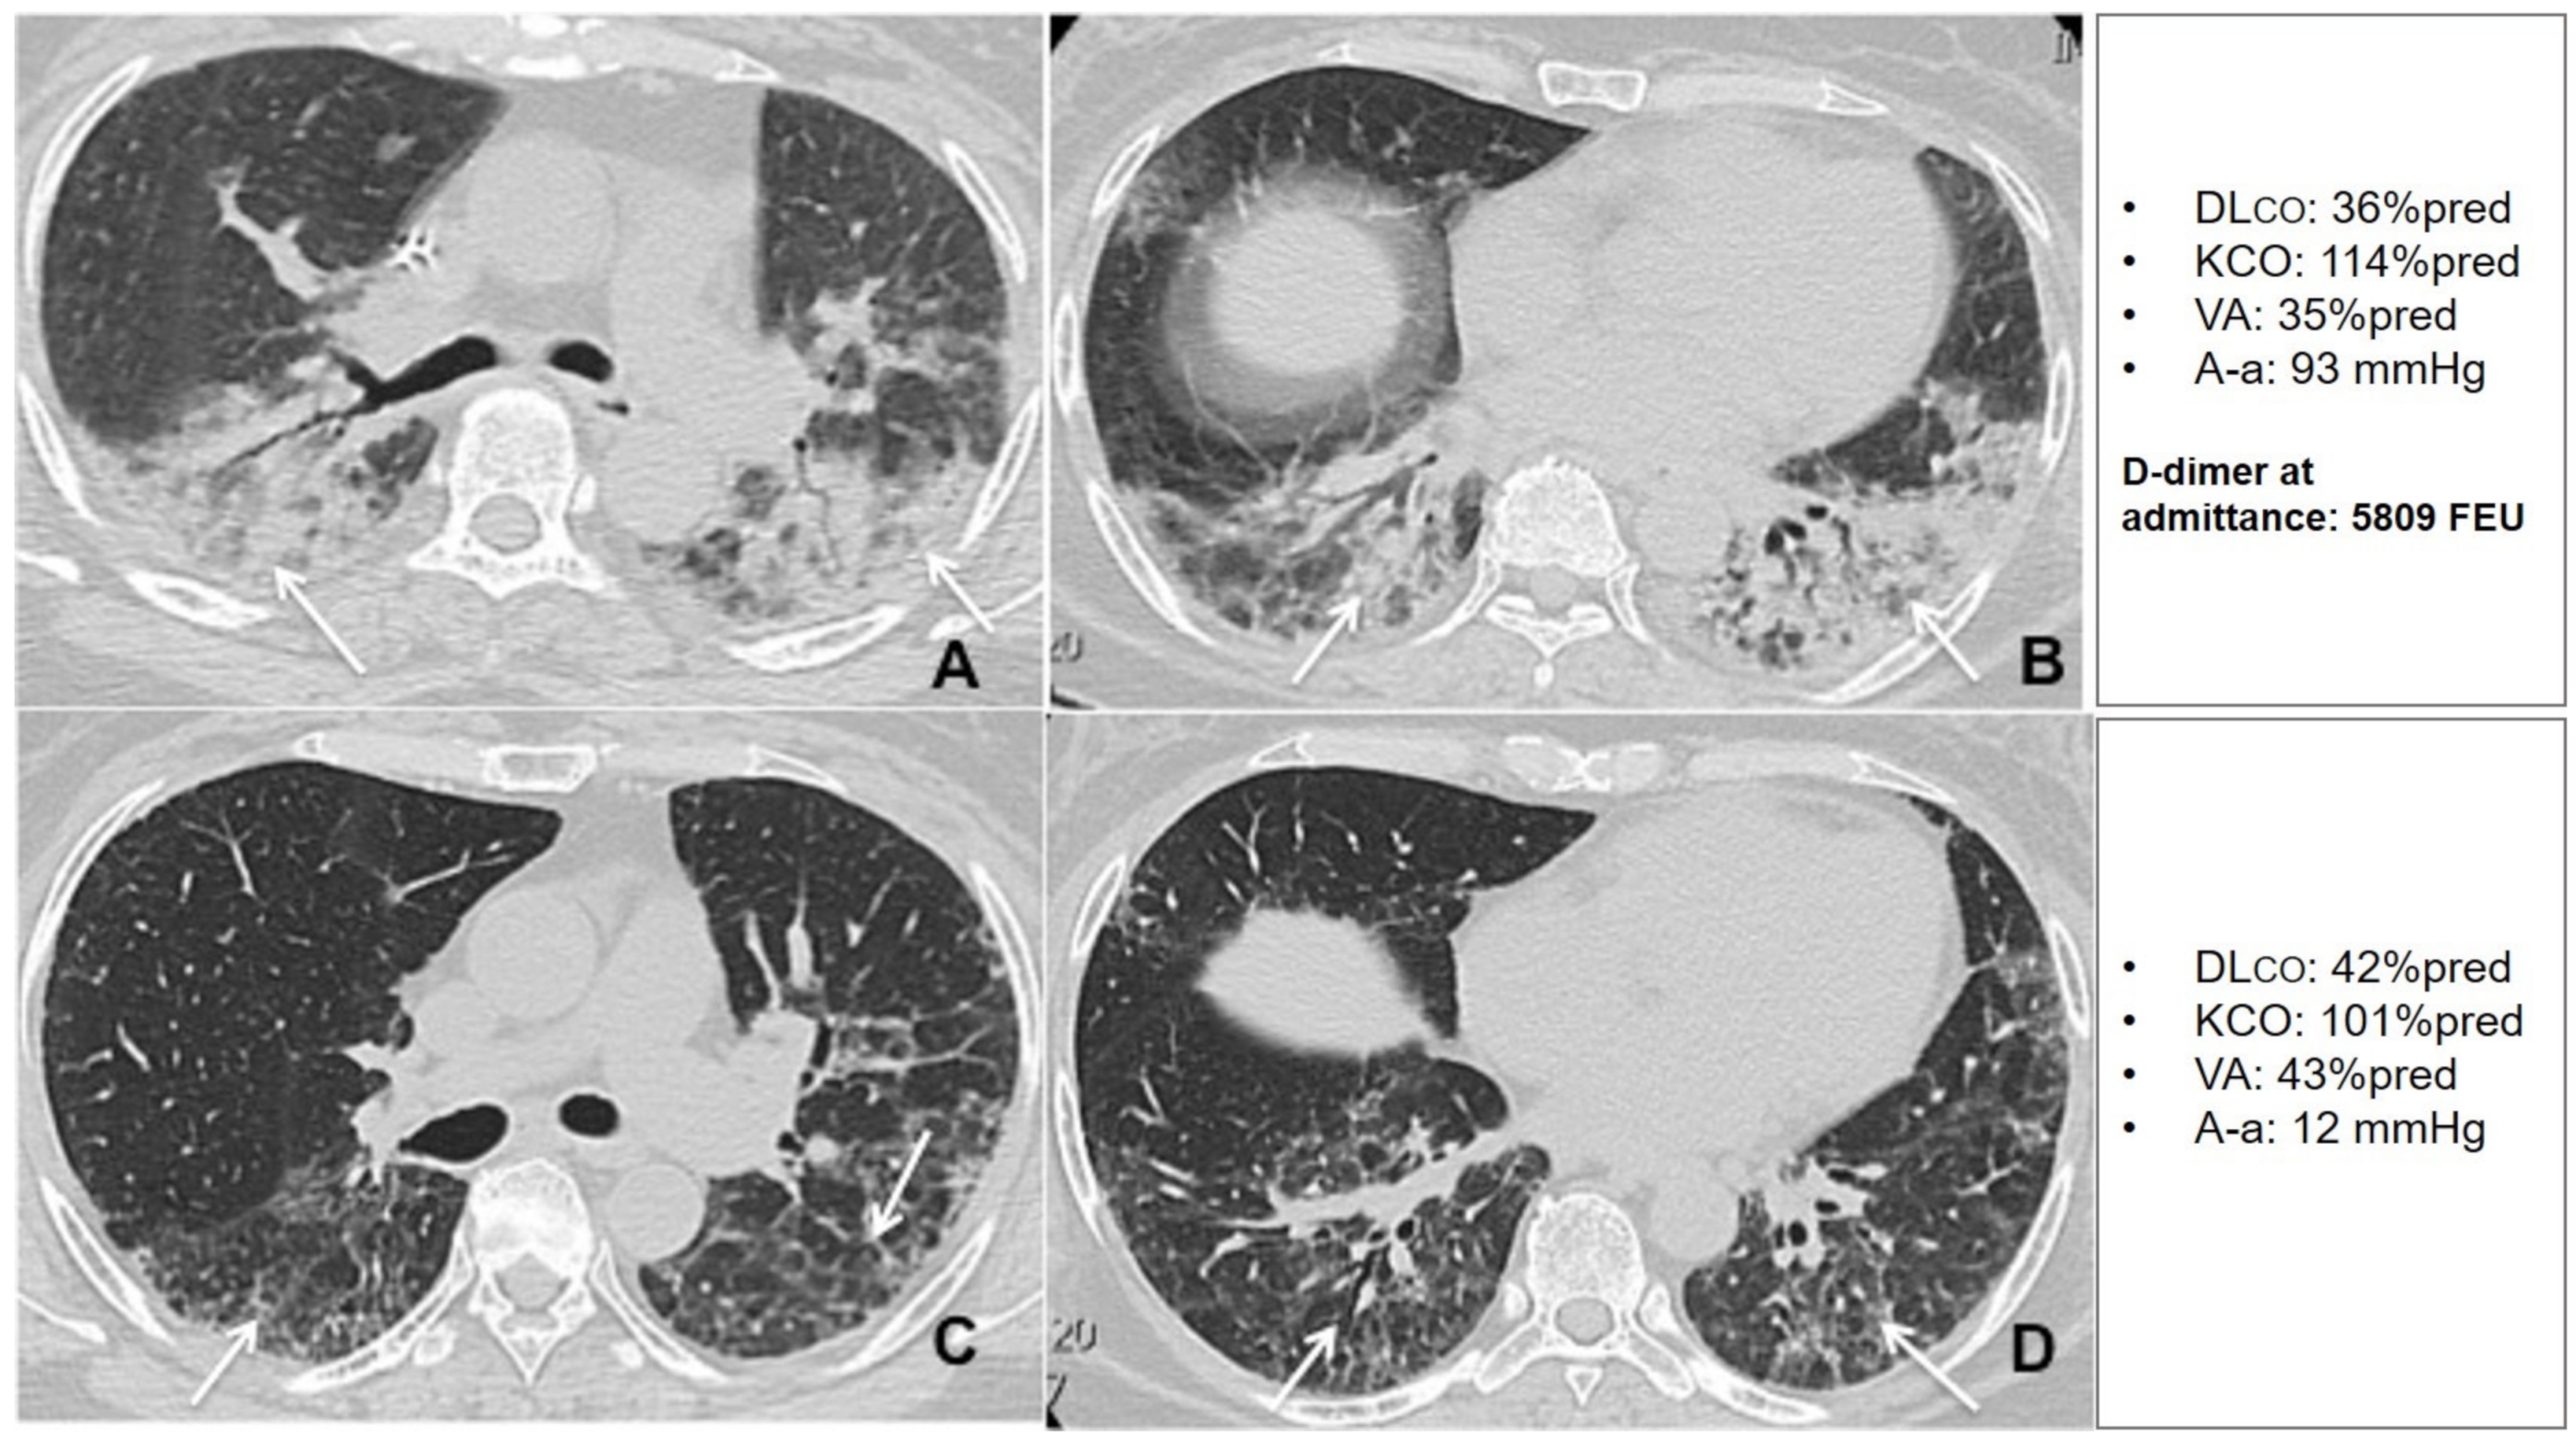

Figure 8.

Unenhanced thin section axial (A,B) CT images of the lungs obtained the 12th day post-admission in a 57-year-old woman with arterial hypertension and no previous exposure to cigarette smoke, that was admitted to the HDRU with a PaO2/FiO2 of 210 mmHg, rapidly worsened her respiratory status and needed invasive mechanical support for 8 days. The images show peripheral posterior GGO and consolidations in both lungs, with predilection for posterior areas (arrows). Unenhanced axial (C,D) CT images of the same patient 6 weeks post-discharge show residual interlobular septal thickening with intralobular lines (arrows) with resolution of previous GGO and consolidation. The patient had a high D-dimer at admission and showed very limited changes in DLco during the recovery period.